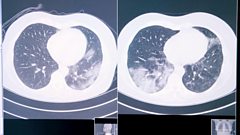

We see one of the world's first trials of an artificial intelligence algorithm to help doctors quickly distinguish between Covid-19 and cancer treatment toxicity on scans. These decisions could be a matter of life and death and are challenging for the human eye to detect. Click scrubs up to meet the many-armed robot on wheels that's making keyhole surgery more available. And we learn how a therapy app and electricity emitting headset could provide better at-home treatment for those living with depression.

How AI is helping lung cancer patients